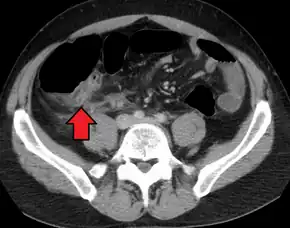

Computed tomography

Where it is readily available, computed tomography (CT) has become frequently used, especially in people whose diagnosis is not obvious on history and physical examination. Although some concerns about interpretation are identified, a 2019 Cochrane review found that sensitivity and specificity of CT for the diagnosis of acute appendicitis in adults was high.[59] Concerns about radiation tend to limit use of CT in pregnant women and children, especially with the increasingly widespread usage of MRI.[60][61]

The accurate diagnosis of appendicitis is multi-tiered, with the size of the appendix having the strongest positive predictive value, while indirect features can either increase or decrease sensitivity and specificity. A size of over 6 mm is both 95% sensitive and specific for appendicitis.[62]

However, because the appendix can be filled with fecal material, causing intraluminal distention, this criterion has shown limited utility in more recent meta-analyses.[63] This is as opposed to ultrasound, in which the wall of the appendix can be more easily distinguished from intraluminal feces. In such scenarios, ancillary features such as increased wall enhancement as compared to adjacent bowel and inflammation of the surrounding fat, or fat stranding, can be supportive of the diagnosis. However, their absence does not preclude it. In severe cases with perforation, an adjacent phlegmon or abscess can be seen. Dense fluid layering in the pelvis can also result, related to either pus or enteric spillage. When patients are thin or younger, the relative absence of fat can make the appendix and surrounding fat stranding difficult to see.[63]